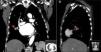

A contrast-enhanced computed tomography scan of the chest showed a pulmonary artery pseudoaneurysm with a maximum diameter of 45 mm at the right middle lobe, which was enhanced by contrast (Figure 1A and B). Pulmonary angiography confirmed the diagnosis (Figure 2A). After consultations with the respiratory medicine and interventional radiology departments, a percutaneous stent graft implantation was planned, in which a 6F multipurpose guiding catheter (Cordis) was placed and a PT2TM guide wire was positioned distal to the aneurysm. Under angiographic control a 3.5 mm×18 mm stent (BeGraft Peripheral Stent Graft System, Bentley Innomed) was placed in the pulmonary artery. This procedure was successful and there were no complications (Figures 2B and C).

During hospitalization, the patient was hemodynamically stable and had no further hemoptysis. She was discharged 16 days after admission, treated with aspirin 100 mg/day, clopidogrel 75 mg/day, warfarin 5 mg (dose set by the hematology department), furosemide 40 mg/day and pantoprazole 20 mg/day. A follow-up chest computed tomography scan performed two months later showed patency of the stent graft in the pulmonary artery, with a completely thrombotic false aneurysm (Figure 3). At seven months of follow-up, no events were recorded.